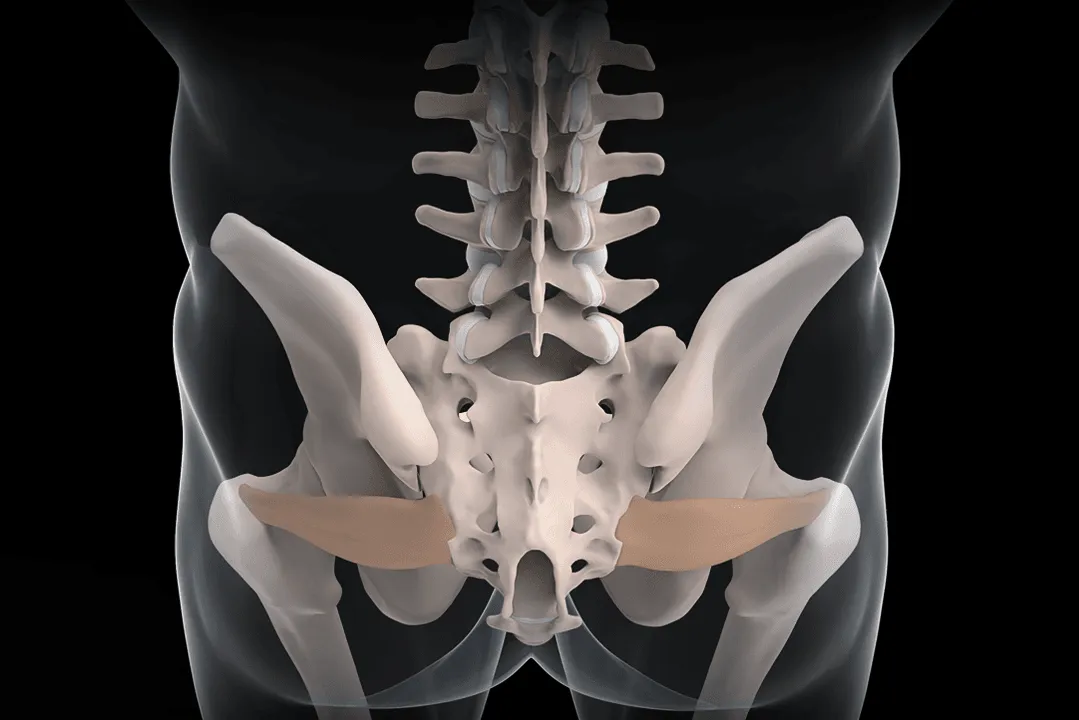

Sacroiliac joint pain and piriformis muscle pain are the third most common causes. These two sources are roughly equal in prevalence. The sacroiliac (SI) joint connects your pelvis to your spine. The piriformis muscle runs from your sacrum to your hip and can become chronically inflamed from injury.

Sacroiliac Joint Pain

The SI joint connects your pelvis to your spine. Inflammation or arthritis in this joint causes pain in the lower back, buttocks, and sometimes down the leg, often mimicking sciatica.

SI joint pain comes from inflammation within the joint space or from ligamentous injury around the joint. The pain pattern typically includes:

- Lower back and buttock pain on the affected side

- Pain with transitions: sitting to standing, getting out of cars

- Pain with prolonged sitting or standing

- Sometimes radiation into the posterior thigh